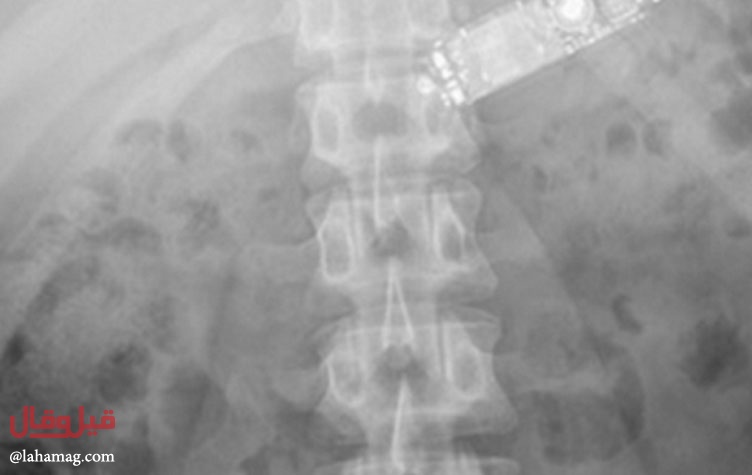

وواجه المسعفون حالة نادرة عندما وجدوه في حالة صعبة، وأظهر فحص الأشعة السينية أن الهاتف موجود في داخل بطنه.

وحاول المسعفون في بداية الأمر إخراج الهاتف عبر إدخال منظار طبي إلى جوف السجين، لكن هذه المحاولة أخفقت.

وأشاروا إلى أن الأمر يتطلب إجراء عملية شق البطن وإخراج الهاتف الذي استقر في المعدة، واستطاعوا إخراجه بعد عملية جراحية تطلبت 18 ساعة.